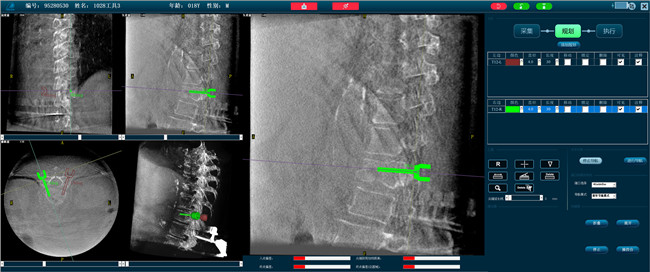

步驟二:手術(shù)實施

在病人體表切開一個長1-2cm的創(chuàng)口,沿骨科機器人的機械臂定位點方向?qū)⒖耸厢槍?dǎo)向套筒,通過創(chuàng)口送至病灶椎體處,并沿套筒方向打入克氏針進行定位。沿導(dǎo)針插入工作套管,取出導(dǎo)針,完成球囊擴張后,通過骨水泥注入器準確地在骨折部位緩慢注入骨水泥,幫助其恢復(fù)椎體的形狀和強度。

骨科機器人應(yīng)用場景